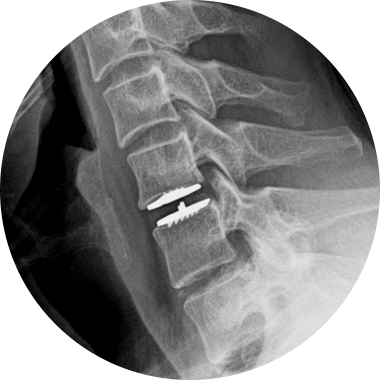

손상된 경추 디스크를 제거한 후, 척추체 사이에 인공디스크를 삽입하는 수술적 치료입니다.

손상된 경추 디스크를 모두 제거하고 빈 공간으로 인공디스크를 삽입하여 본래의 디스크처럼 정상적인 기능을 하도록 합니다.

경추 인공디스크 치환술 후 자유로운 목 움직임